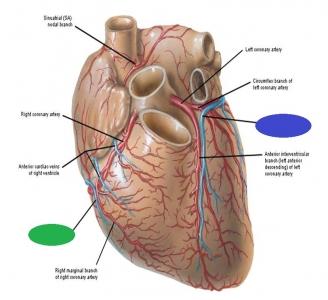

Anterior interventricular valve

Anterior interventricular sulcus

Circumflex branch (of the left coronary artery)

interventricular branch of the left coronary artery. = left anterior descending artery (LADA))

Left/right coronary artery

green